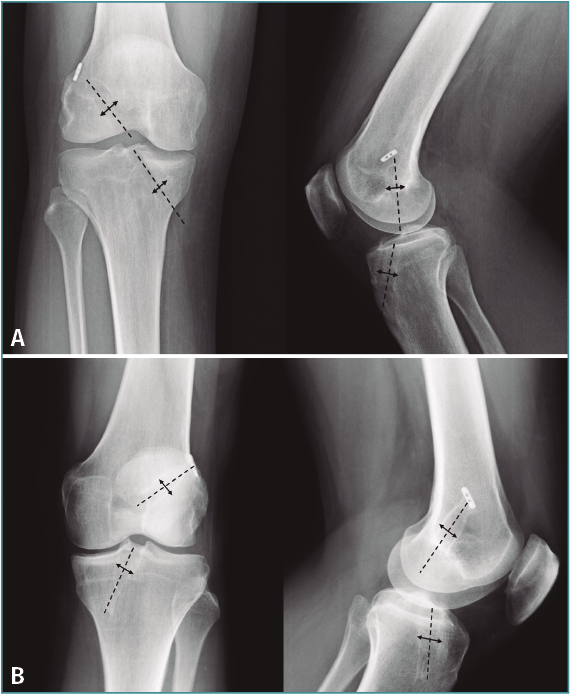

El ensanchamiento óseo de los túneles se calculó comparando la medición del diámetro comprendida entre los márgenes óseos del túnel tanto femoral como tibial en las radiografías AP y lateral del postoperatorio inmediato y tras un mínimo de 6 meses de seguimiento. Esta medición se calculó midiendo la distancia comprendida entre los márgenes escleróticos del túnel formando una línea perpendicular al eje del túnel femoral y tibial, expresada en milímetros. Si el diámetro del control radiográfico del postoperatorio inmediato no fue posible por la escasa visualización de los márgenes, se utilizó el diámetro intraoperatorio del túnel (Figura 2).

Figura 2. Ensanchamiento de túnel femoral y tibial en radiografías anteroposterior y lateral midiendo la distancia comprendida entre los márgenes escleróticos del túnel formando una línea perpendicular al eje del túnel femoral y tibial, expresada en milímetros. A: grupo A (anterógrado); B: grupo R (retrógrado).